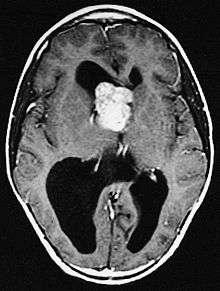

| GFAP stained microscopic section of a subependymal giant cell astrocytoma | |

Subependymal giant cell astrocytoma (SEGA, SGCA, or SGCT) is a low-grade astrocytic brain tumor (astrocytoma) that arises within the ventricles of the brain.[1] It is most commonly associated with tuberous sclerosis complex (TSC). Although it is a low-grade tumor, its location can potentially obstruct the ventricles and lead to hydrocephalus.